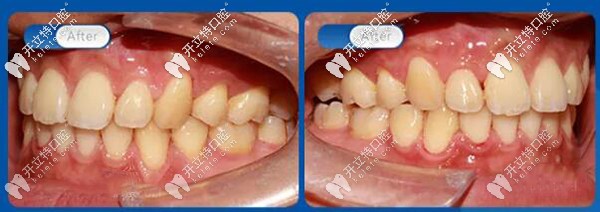

從口內(nèi)45°左右側(cè)面照對比可以看到上牙列不齊,牙弓前凸,磨牙深覆蓋,上下牙列重度擁擠,上下咬合關(guān)系不協(xié)調(diào)。

上下咬合關(guān)系不協(xié)調(diào)

45度看,解除牙列擁擠,解除牙弓前凸,解除磨牙深覆蓋,恢復(fù)正常咬合關(guān)系。

解除牙弓前凸